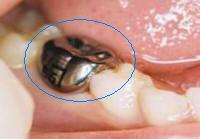

5 |

Coronaa inoxidable |